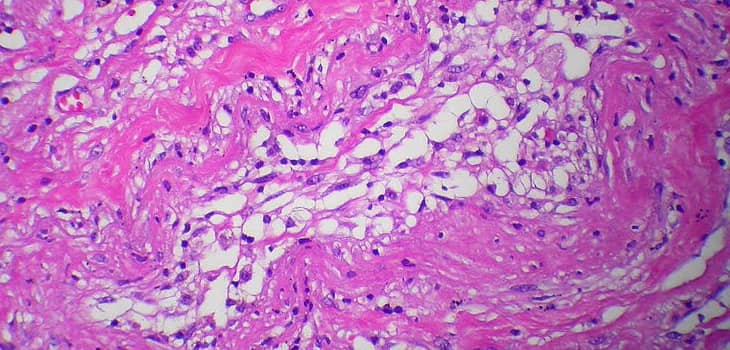

Approvato dall’FDA e premiato come “Best New Technology in Sports Medicine”, Lipogems ortopedia è oggi un trattamento imprescindibile per atleti professionisti e sportivi evoluti. Grazie all’uso del tessuto adiposo autologo, Lipogems consente di rigenerare in modo naturale lesioni al ginocchio, alla spalla, all’anca, condropatie e tendinopatie, favorendo una guarigione profonda, riducendo il dolore e ottimizzando il recupero. Sempre più diffuso tra le equipe mediche sportive, è utilizzato sia per prevenire l’usura articolare che come supporto nel recupero post-operatorio, riducendo le recidive e migliorando i risultati funzionali nel lungo termine. In un contesto dove il tempo di recupero è cruciale, Lipogems si impone come la soluzione naturale, rigenerativa e scientificamente validata. Disponibile anche a Milano presso Image Regenerative Clinic, con esperienze documentate e opinioni positive da parte di atleti di alto livello. La medicina sportiva ha già cambiato direzione: oggi non si sostituisce, si rigenera.

Lipogems Sport è la soluzione avanzata per il trattamento di infortuni sportivi complessi e resistenti alle terapie tradizionali. Tendinopatie: epicondilite, tendinite achillea, rotulea e della cuffia dei rotatori per recupero funzionale completo. Lesioni cartilaginee: condropatie di ginocchio, anca, caviglia per evitare interventi demolitivi. Distorsioni croniche: instabilità di caviglia e ginocchio con persistente dolore e limitazione funzionale. Lesioni muscolari: stiramenti e strappi ricorrenti che compromettono le performance atletiche. Overuse syndrome: sovraccarico da allenamento intensivo con dolore cronico articolare. Artrosi precoce: degenerazione articolare in atleti giovani per preservare la carriera sportiva.